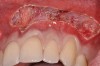

The authors have introduced a laser-assisted vestibuloplasty approach (LAVA) procedure that is designed to prevent recurrent recession after surgical correction, which has been reported in the literature.29,38 This first involves a flap procedure for insertion of the dermal matrix graft material to be used to achieve root coverage and increase zones of existing attached keratinized tissues. To complete the vestibuloplasty procedure, the surgeon separates the mucosal tissues apical to the preexisting mucogingival junction in the area of the teeth exhibiting gingival recession. The authors advocate using a Nd:Yag laser with a power setting at 5 watts to accomplish the vestibuloplasty and release any excessive muscle attachments or frenal pulls in the affected areas (Figure 3).

Fig 3. Example of laser-assisted split-thickness

vestibuloplasty.

Figure 3

Fig 4. V-type incision to preserve the crestal portion of the papilla.

Figure 4